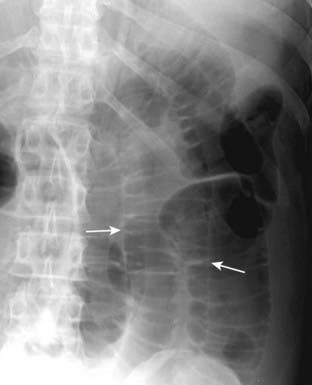

Figure 15-7 Rigler sign.

When air fills the peritoneal cavity, both sides of the bowel wall will be outlined by air (solid white arrows) making the wall of the bowel visible as a discrete line. This is known as Rigler sign and indicates the presence of a pneumoperitoneum.

imagePitfall: When dilated loops of small bowel overlap each other, they may occasionally produce the mistaken impression that you are seeing both sides of the bowel wall (Fig. 15-8).